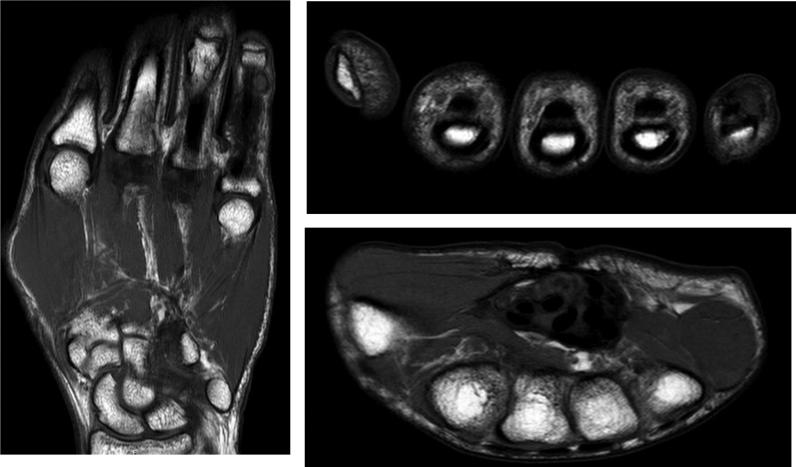

Diffuse pigmented villonodular synovitis is characterized by synovial inflammation and hemosiderin deposition. It mainly occurs in adults, with the hip and knees being the most common sites of involvement. It is associated with high recurrence rates, with open synovectomy being the most common treatment method to avoid recurrence. Few cases of diffuse pigmented villonodular synovitis have been reported in pediatric patients, especially in uncommon locations such as the hand. This case presents pathology-confirmed diffuse pigmented villonodular synovitis in the hand of a pediatric patient with multiple recurrences despite adequate surgical margins. The patient underwent mass excision with adjuvant radiation treatment after his last recurrence, with excellent functional outcomes and no recurrence at the five-year follow-up.

弥漫性色素沉着绒毛结节性滑膜炎的特征为滑膜炎症和含铁血黄素沉积。它主要发生于成年人,髋部和膝部是最常受累的部位。其复发率较高,开放性滑膜切除术是避免复发的最常用治疗方法。小儿患者中弥漫性色素沉着绒毛结节性滑膜炎的病例报道较少,尤其是在手部等不常见部位。本病例呈现了一名小儿患者手部经病理证实的弥漫性色素沉着绒毛结节性滑膜炎,尽管手术切缘足够,但仍多次复发。该患者在最后一次复发后接受了肿块切除及辅助放疗,功能预后良好,五年随访时无复发。